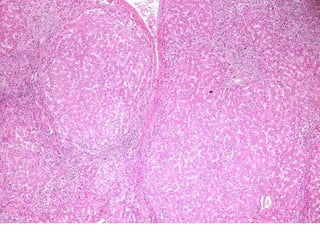

BS09-10453 55 yo, female.  Clinical history:  Elevated ALT/AST. Viral serologies negative.

BS09-10453:  Dx: Chronic hepatitis, with severe activity (bridging necrosis) and portal fibrosis, ? autoimmune hepatitis vs. drug/toxin mediated injury. Corresponds to: Modified Ishak stage 1/4 Metavir F1

BS09-10453 55 yo,female. Clinical history: Elevated ALT/AST. Viral serologies negative.

BS09-10453: Dx:Chronic hepatitis, with severe activity (bridging necrosis) and portal fibrosis, ? autoimmune hepatitis vs. drug/toxin mediated injury. Corresponds to: Modified Ishak stage 1/4 Metavir F1